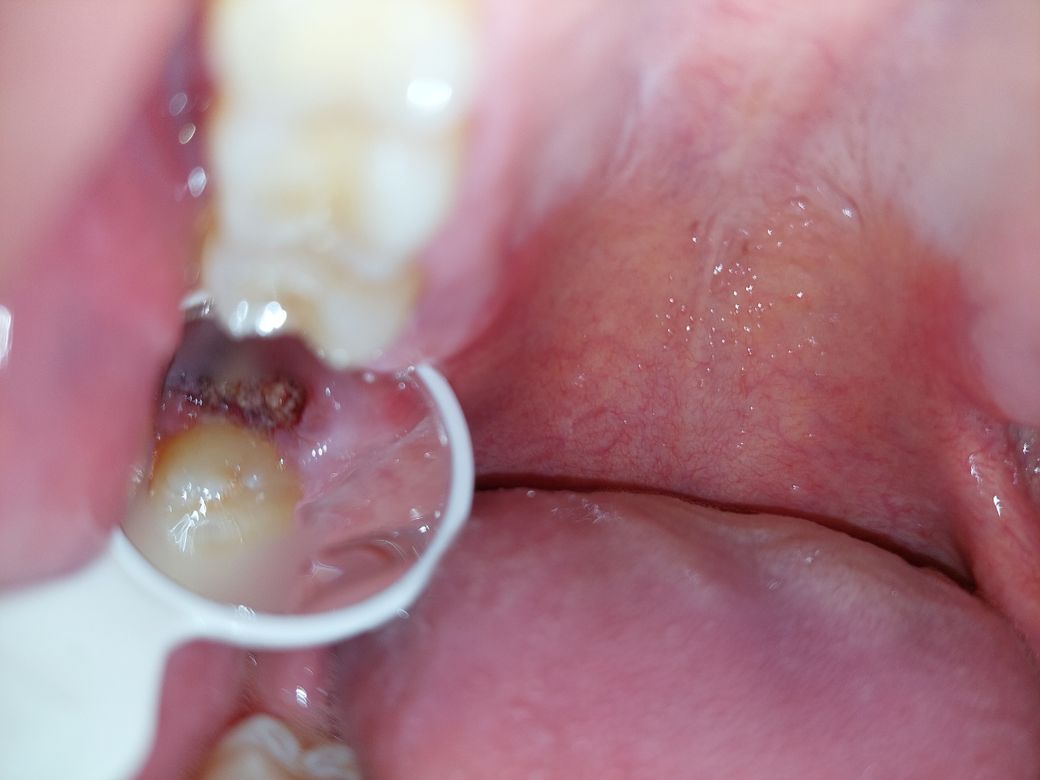

안녕하세요. 오늘 사랑니 발치하고 3시간 정도 있다 발치한 곳을 확인해 보았더니, 안에 하얀 덩어리들이 있는 것을 보았습니다. 뽑는 과정에서 사랑니를 돌려서 뽑은 듯한 느낌이 들었어서 혹시나 사랑니 뿌리가 남은 것이 아닐까 걱정이 되어 질문 드립니다.

아래는 제가 찍은 사진입니다.

사진상으로는 정확히 알수가 없고 엑스레이 사진을 찍어보면 뿌리가 남은건지 제대로 알수 잇습니다. 하얗게 보이는건 발치를 하고 나서 그쪽부위에 치유되는과정중에 생기는거니 크게 걱정은안하셔도 됩니다.

혈병이 보이는것일수도 있고, 지혈제를 넣은것일수도 있습니다.

직접봐야 알 수 있겠지만 치아뿌리가 남아있는 것으로는 보이지 않고 사진상으로는 상피세포가 회복을 위해 생기고 있는 것으로 보입니다.